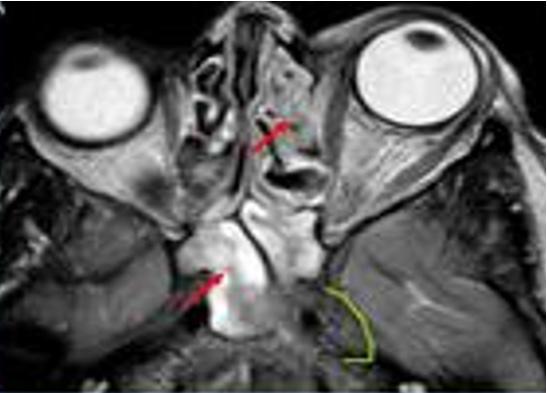

Fractura de órbita

PISO DE ÓRBITA GENERALIDADES

Es la zona más débil y por tanto el más común

Traumatismo contuso de alta velocidad en el globo ocular (Por un puñetazo, una pelota de tenis)

DIAGNÓSTICO

Dolor, edema y / o equimosis peri orbitarios unilaterales

Enoftalmos o proptosis

(ENAM EXTRA 2021)

Tratamiento

Borde orbital " step-off " Movimiento ocular restringido en el plano vertical (hacia arriba) Diplopía (ENAM EXTRA 2021)

Defecto pupilar aferente y alteración de la agudeza visual. Signo de lágrima en la radiografía.

deprimida del suelo orbitario derecho (fractura por estallido) se acompaña de una hernia de grasa orbitaria en la cara superior del seno maxilar y atrapamiento del músculo recto inferior (signo de la lagrima).

Figura 71. Los 7 huesos que forman parte de la órbita, recordar que la lámina papirácea forma parte del hueso etmoides Figura 72. Fractura del piso o suelo orbitario Una fractura Figura 73. Fractura del piso o suelo orbitario Prueba de motilidad ocular. La mirada hacia arriba del ojo derecho está restringida como resultado del atrapamiento del recto inferior.